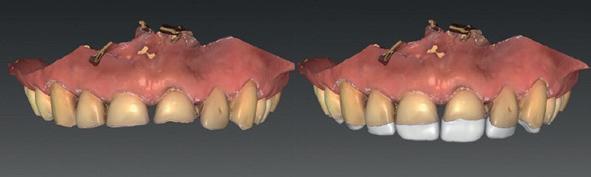

Een 47-jarige vrouw wordt aan het einde van het orthodontische traject door haar eigen tandarts naar mij verwezen voor een intake en eventuele behandeling. Bij mevrouw zijn elementen 12 en 22 afwezig. De 13 en 23 zijn gemesialiseerd. Haar eigen tandarts vraagt of ik het front met composiet kan restaureren om weer een harmonieuze glimlach te krijgen (Afbeelding 1).

Tijdens de intake wordt een complete lichtfoto status gemaakt om de positie van de elementen goed in kaart te brengen en een behandelplan op te kunnen stellen. Op de close-up foto van het bovenfront (afbeelding 2) zien we dat er sprake is van slijtage aan element 11. Elementen 12 en 22 zijn afwezig en elementen 13 en 23 zijn gemesialiseerd. Tussen element 11 en 13 is er sprake van een diasteem. Dit diasteem is niet aanwezig aan de andere zijde (afbeelding 3).

Dit zorgt voor een lastige situatie, omdat bij het sluiten van dit diasteem (dit is de wens van de patiënt) elementen 13 en 11 breder zullen worden dan elementen 21 en 23. Dit is één van de redenen waarom ik patiënten altijd graag aan het einde van het orthodontist traject wil zien. Op dat moment is het nog mogelijk om kleine wijzigingen door te voeren, voordat de beugel definitief wordt verwijderd. Na de intake stuur ik een terugrapportage naar de orthodontist waarbij ik vraag om de elementen zo te positioneren dat de ruimte beter verdeeld is.

Ik zie mevrouw een aantal weken later terug voor evaluatie (afbeelding 4). Er is een klein centraal diasteem ontstaan en daardoor is het diasteem tussen de 11 en 13 ook kleiner geworden. Tussen de 21 en 23 is geen diasteem aanwezig (afbeelding 5), waardoor er hoogstwaarschijnlijk wel iets breedte verschil zal zijn tussen de linker- en rechterzijde.

Met composiet wordt een snelle mock-up gemaakt om te beoordelen of ik in deze situatie goed kan uitkomen met de ruimte, of dat we wellicht de elementen nog meer moeten verplaatsen (afbeelding 6). Mevrouw is zeer tevreden met de snelle mock-up en daarom wordt besloten dat de orthodontische behandeling afgerond kan worden. Eventuele verschillen in breedte kunnen we proberen optisch zoveel mogelijk te maskeren.

Nadat de vaste apparatuur verwijderd is (afbeelding 7 en 8), zie ik mevrouw voor het maken van een afdruk/scan ten behoeve van een wax-up. Aangezien ik in deze casus wil werken met de injectietechniek, is een wax-up noodzakelijk.